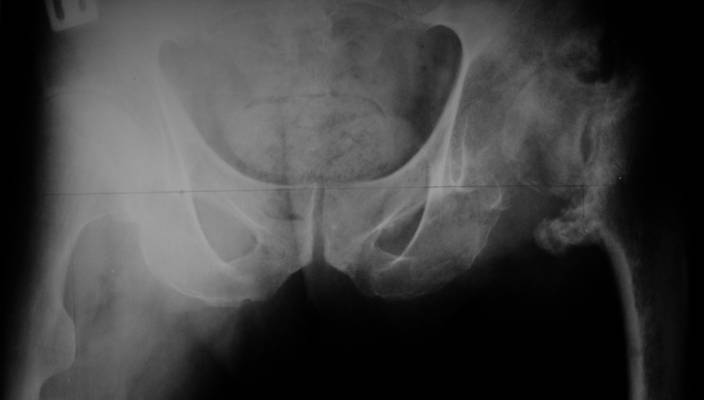

AV> опираясь на стул. На ногу не наступает. Укорочение 8 см. Иногда

А за счет чего такое укорочение? По снимку не видно соответствующего дефекта. Ну плюс приводящая контрактура - но все равно как-то уж больно много. Может, сделать снимки и таза обзорный с обоими проксимальными отделами бедра, и коенный суставов с приложенной линейкой какой?

Судя по снимку, максимум истинное укорочение около 4 см, что может быть коррегировано интраоперационно. Вопрос в другом: куда ставить ацетабулярный компонент в истинную или во вновь сформированную ( впадина диспластичная).

Невозможно не согласиться с Анатолием, чтобы заниматься адекватным планированием как минимум прямая проекция таза должна быть сделана, как

максимум для оценки состояния мышц( насколько реально возможно низвести бедро) прямая проекция таза с тракцией за больную ногу.

The X ray that you provided does not show 8 cm of shortening. Perhaps you could send one showing the whole pelvis and proximal femurs.

I agree with Dr Eid's comments. The origin of the 8 cm leg length difference is a puzzle. Is this a clinical measurement? In that case contracture of the joint might affect the measurement. Can we see an AP pelvis to include both hip joints (including a calibration object with a known length) so that the difference in leg lengths that can be ascribed to the hip deformity and bony reabsorption can be measured. This sort of xray will help with templating for the TJR also. I would be very tempted to do a one stage procedure and accept some shortening. Shoe lifts should take care of a 3-4 cm difference.

До травмы проблем с ногой не было. Укорочения, болей и т.п. не отмечал. Сегодня перемерял укорочение - меньше 7 см намерять не

По уровню малых вертелов (с учетом рентгеновского увеличения) получается 5 см. Клинически ногу низвести путем тракции невозможно. Из движений - сгибание до 40*, остальные движения "символические".

Ортопедическое укорочение пострадавшей ноги может быть и 7, и 10 см. за счет контрактур в тазобедренном суставе, а вот истинное укорочение, судя по представленным рентгенограммам, вряд ли больше 4 см.